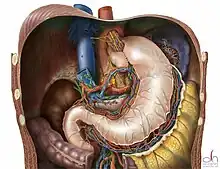

Diagram of a Nissen fundoplication. | |

In a fundoplication, the gastric fundus (upper part) of the stomach is wrapped, or plicated, around the lower end of the esophagus and stitched in place, reinforcing the closing function of the lower esophageal sphincter (LES). The esophageal hiatus is also narrowed down by sutures to prevent or treat concurrent hiatal hernia, in which the fundus slides up through the enlarged esophageal hiatus of the diaphragm. The surgeon should begin with ligating and dividing the short gastric arteries.[9]

In a Nissen fundoplication, also called a complete fundoplication, the fundus is wrapped the entire 360 degrees around the esophagus. In contrast, surgery for achalasia is generally accompanied by either a Dor or Toupet partial fundoplication, which is less likely than a Nissen wrap to aggravate the dysphagia that characterizes achalasia. In a Dor (anterior) fundoplication, the fundus is laid over the top of the esophagus; while in a Toupet (posterior) fundoplication, the fundus is wrapped around the back of the esophagus.